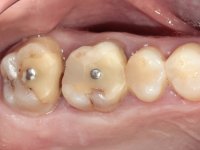

In a first phase, a 2-element bridge in Zr was proposed. in teeth 17 and 16. When 4 years later, an abscess appeared in tooth 26, the patient was proposed to remove the bridge, remove the intra-radicular posts and perform a retreatment of the endodontic treatments and put the bridge back. It was possible to do what we set out to do, but 1 year after this procedure, with the appearance of a new abscess, the extraction of tooth 26 was proposed. With this extraction, the patient was proposed to make a bridge in Zr. of 3 elements, with teeth 27 and 25 as abutments and 26 as a pontic.

Teeth 17 and 16 were prepared for the fabrication of a 2-element Zr bridge. The impression was performed with a double mixing technique and a monolithic bridge in Zr was made in the laboratory. 4 years later, an abscess appeared in the apical area of tooth 26. It was decided to remove the bridge, remove the intra-radicular posts and retract the endodontic treatments of teeth 17 and 16. The removal of the bridge was carried out by making two cervical cavities. in the palatal area of the bridge and with a microluxator, disinsertion movements were performed. The intra-radicular posts were removed using fine drills and an ultrasound tip. The bridge was provisionally cemented and the patient was referred to a fellow endodontist for endodontic retreatment. After the retreatment, the intraradicular posts were placed again and the bridge was definitively cemented. One year later, a new abscess appears, possibly related to a root fracture. The bridge was sectioned between tooth 27 and 26 and tooth 26 was extracted and the crown of 27 was provisionally cemented. 3 months later, teeth 27 and 25 were prepared and a temporary bridge was made in dual polymerization resin. Then, an impression was made using the double mixing technique and a 3-element bridge in Zr was made in the laboratory. It was permanently cemented in the mouth with resin-reinforced glass ionomer cement.